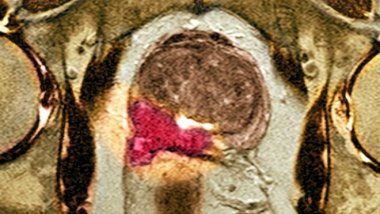

Cervical cancer, threat to women'lives, detected quickly as Chisinau hospital equipped modern microscopes